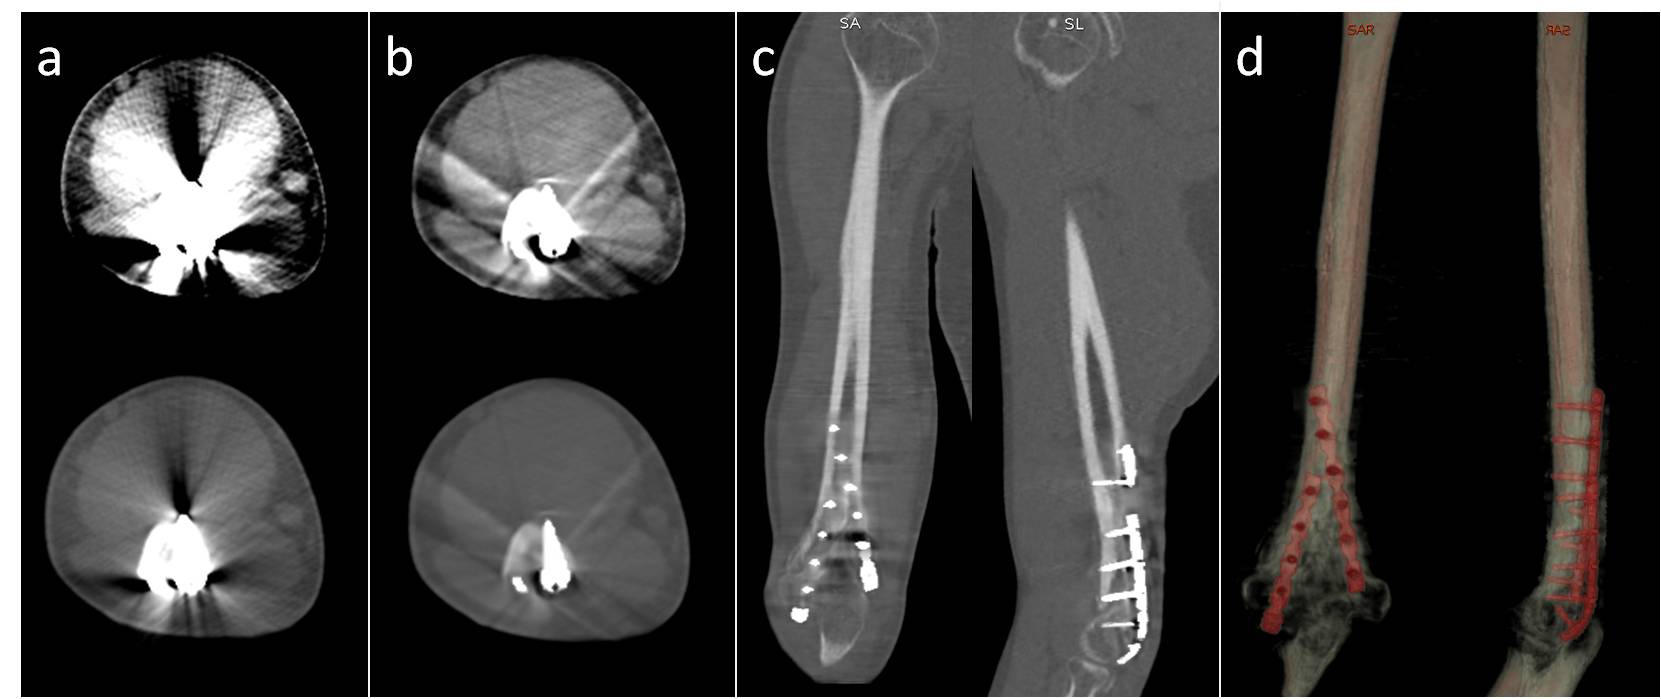

6. Wang Y, Qian B, Li B, Qin G, Zhou Z, Qiu Y, Sun X, Zhu B. Metal artifacts reduction using monochromatic images from spectral ct: Evaluation of pedicle screws in patients with scoliosis. European journal of radiology. 2013;82:e360-366

17. Guggenberger R, Winklhofer S, Osterhoff G, Wanner GA, Fortunati M, Andreisek G, Alkadhi H, Stolzmann P. Metallic artefact reduction with monoenergetic dual-energy ct: Systematic ex vivo evaluation of posterior spinal fusion implants from various vendors and different spine levels. European radiology. 2012;22:2357-2364

19. Liu PT, Pavlicek WP, Peter MB, Spangehl MJ, Roberts CC, Paden RG. Metal artifact reduction image reconstruction algorithm for ct of implanted metal orthopedic devices: A work in progress. Skeletal radiology. 2009;38:797-802